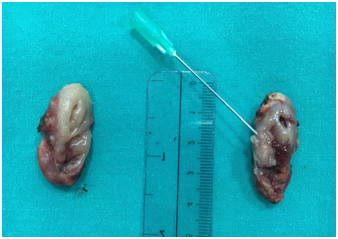

The patient was suggested to undergo tonsillectomy. Routine preoperative investigations were within normal limits and total surgical excision of the lesion through bilateral tonsillectomy was performed under general anesthesia. After completion of the tonsillectomy, both the specimens from the right and left tonsils measured approximately 3,5 cm x 2 cm x1.5 cm. Gross examination revealed a grey, irregular surfaced and 1x0,5 cm measured mass on the midline of left side tonsil (Figure 1). No other lesion was seen on the examination of the contralateral tonsil. Histopathologic examination of the left side revealed tonsilar tissue with chronic inflammation and lobules of mucous secreting salivary acini with ducts adjacent (HSG tissue) and musculary fibers to the surface squamous epithelium of the tonsilar tissue (Figures 2) (Figure 3). Histopathologic examination of the right side revealed only tonsilar tissue with chronic inflammation. A diagnosis of HSG in relation to tonsils was given. Postoperative period was uneventful and recovery was good. A year follow-up revealed no evidence of recurrence and no new relevant symptoms.

Figure 1 Gross specimen, right and left tonsils. Needle shows an exophytic grey, irregular surfaced tonsillar mass on the left tonsil.